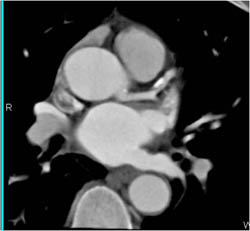

View From the Spine Forward - Nice Pulmonary Veins